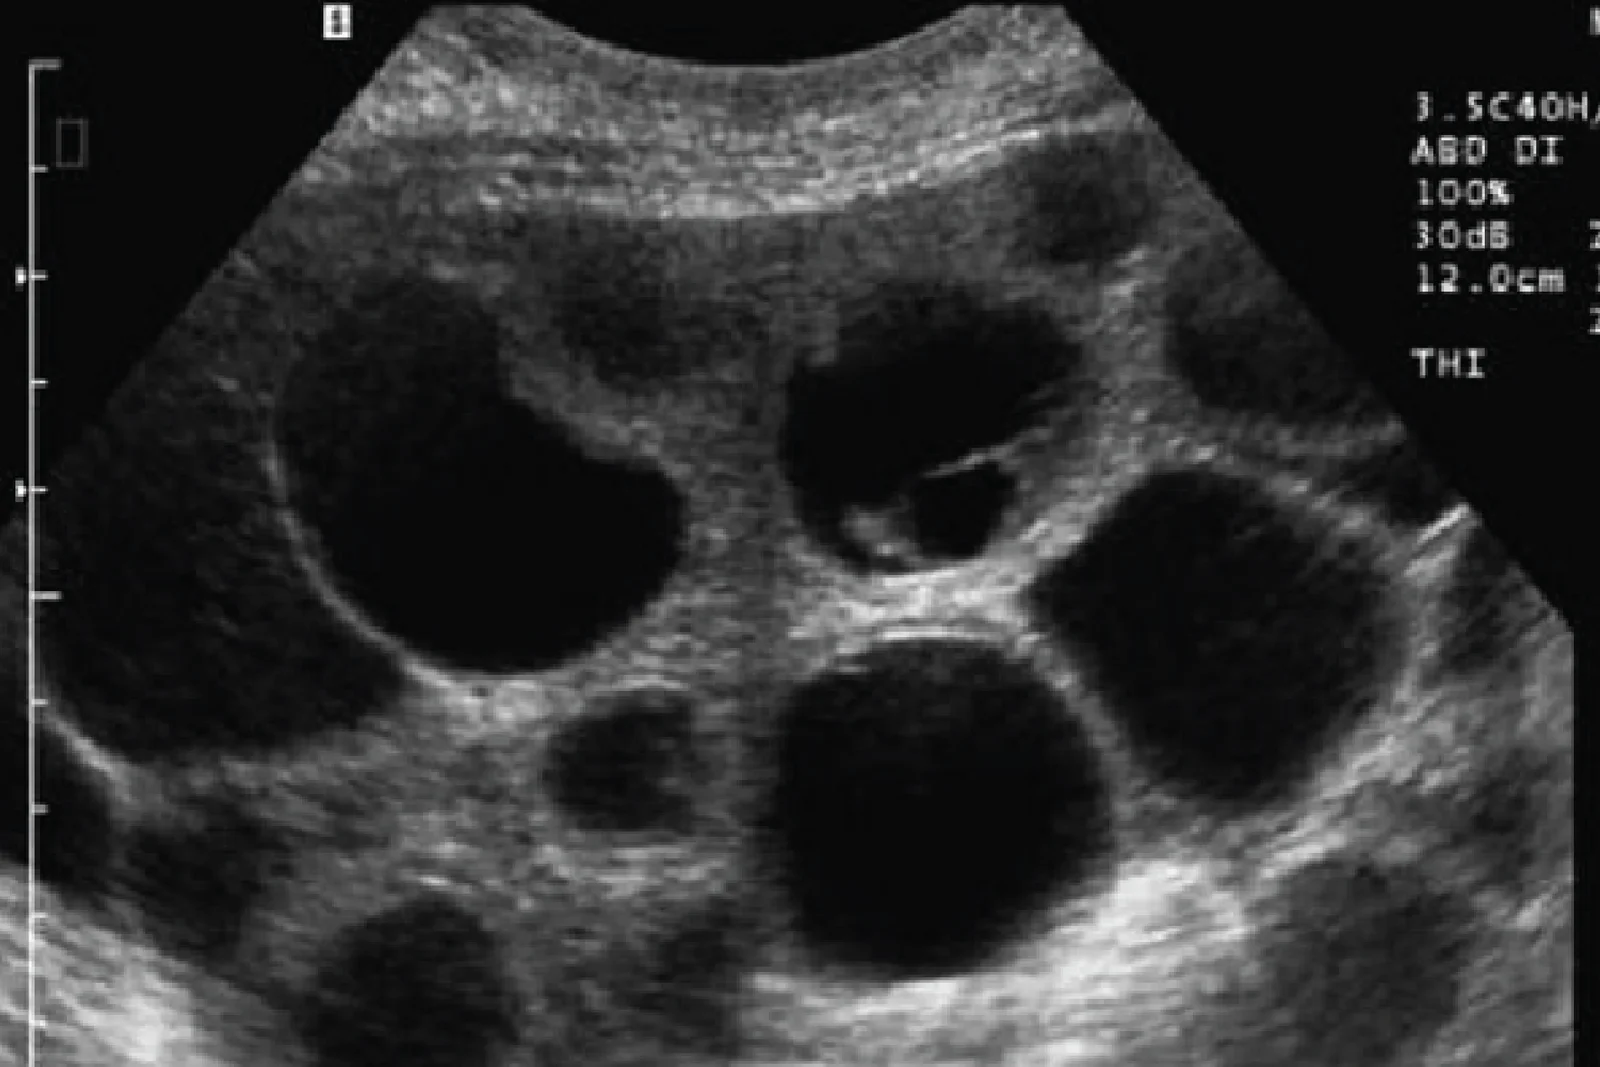

试管腹水 OHSS